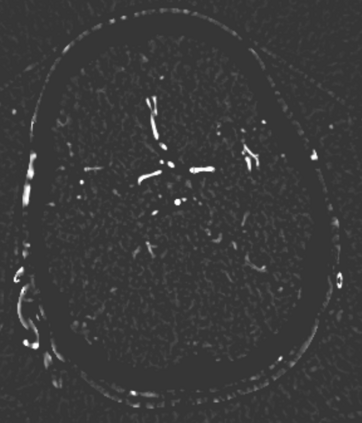

During the diagnosis of ischemic strokes, the Circle of Willis and its surrounding vessels are the arteries of interest. Their visualization in case of an acute stroke is often enabled by Computed Tomography Angiography (CTA). Still, the identification and analysis of the cerebral arteries remain time consuming in such scans due to a large number of peripheral vessels which may disturb the visual impression. In previous work we proposed VirtualDSA++, an algorithm designed to segment and label the cerebrovascular tree on CTA scans. Especially with stroke patients, labeling is a delicate procedure, as in the worst case whole hemispheres may not be present due to impeded perfusion. Hence, we extended the labeling mechanism for the cerebral arteries to identify occluded vessels. In the work at hand, we place the algorithm in a clinical context by evaluating the labeling and occlusion detection on stroke patients, where we have achieved labeling sensitivities comparable to other works between 92\,\% and 95\,\%. To the best of our knowledge, ours is the first work to address labeling and occlusion detection at once, whereby a sensitivity of 67\,\% and a specificity of 81\,\% were obtained for the latter. VirtualDSA++ also automatically segments and models the intracranial system, which we further used in a deep learning driven follow up work. We present the generic concept of iterative systematic search for pathways on all nodes of said model, which enables new interactive features. Exemplary, we derive in detail, firstly, the interactive planning of vascular interventions like the mechanical thrombectomy and secondly, the interactive suppression of vessel structures that are not of interest in diagnosing strokes (like veins). We discuss both features as well as further possibilities emerging from the proposed concept.